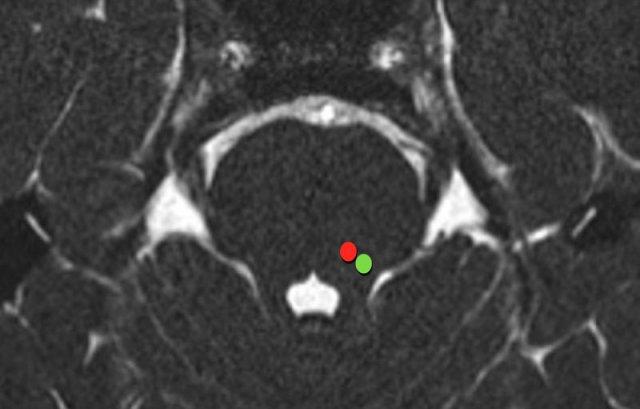

Dây thần kinh sinh ba xuất phát từ hai nhân riêng biệt trong cầu não: nhánh cảm giác từ nhân cảm giác (chấm xanh) và nhánh vận động từ nhân vận động (chấm đỏ).

Nhân cảm giác nằm ở phía bên trong vùng mái, phía trước-bên so với não thất bốn (chấm xanh).

Nhân vận động nằm ở phía trước-trong so với nhân cảm giác (chấm đỏ).